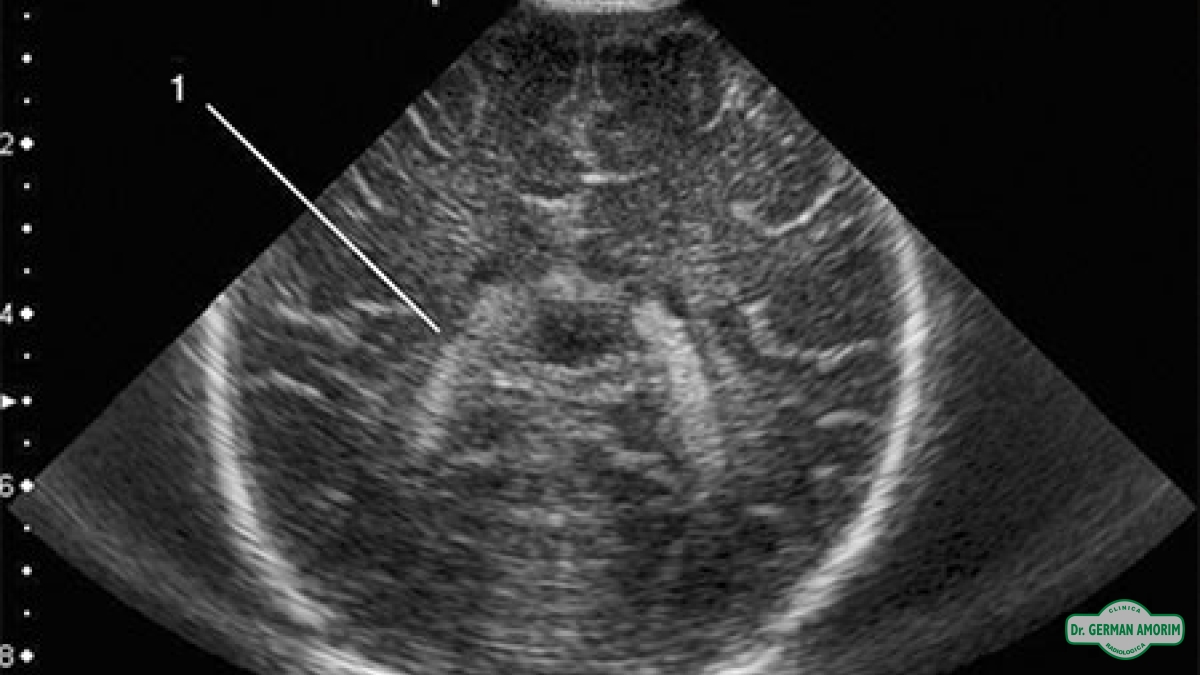

Es hacer una ecografía a través de las fontanelas. Las fontanelas son los espacios entre los huesos del cráneo de los recién nacidos y de los lactantes. Permiten que la cabeza pueda amoldarse y pasar a través el canal del parto, Y que el cerebro del bebé tenga espacio de sobra para que se pueda desarrollar.

En el caso de la ecografía, las fontanelas serían como las ventanas que nos dejan “ver” lo que hay dentro del cráneo usando las sondas adecuadas. Por lo general, la fontanela anterior (la que está en la parte superior de la cabeza) es la que más información nos puede dar. Tanto en recién nacidos como en lactantes y prematuros. También es posible usar las otras fontanelas como la que hay en la parte posterior de la cabeza y a los lados, detrás de las orejas.